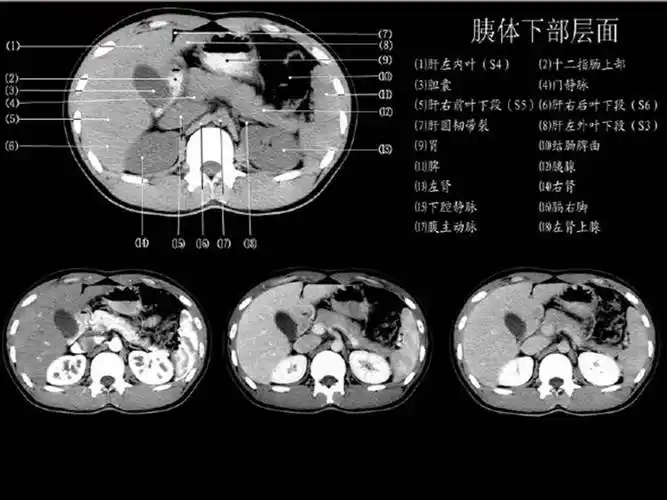

「高清解剖」腹部ct影像学解剖图谱(肝脏分叶分段)

【ppt】正常肝脏ct解剖 – 影像ppt

couinaud肝脏分段系统ct图谱

肝分段-腹部横断面解剖与影像段对照